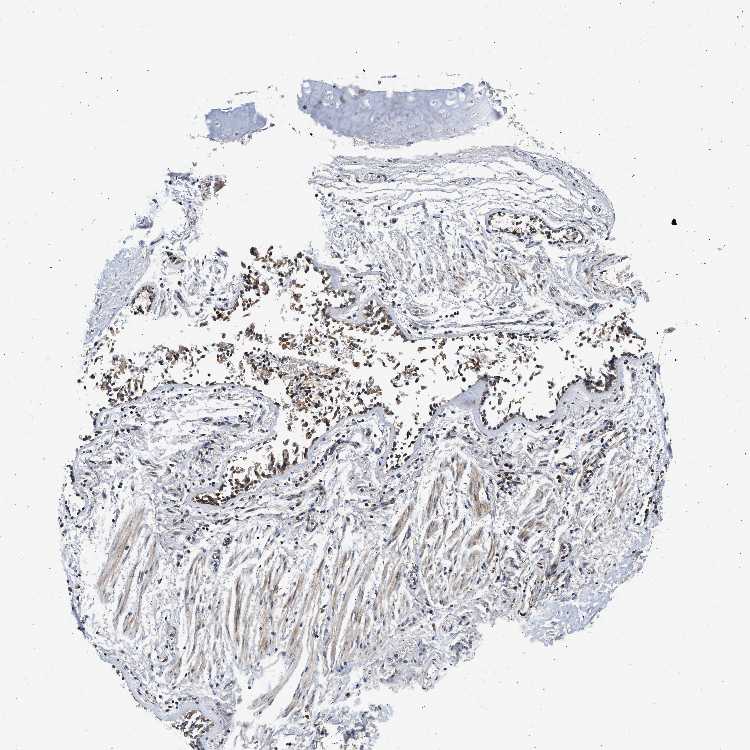

ADIPOSE TISSUE - Antibody stainingi

Antibody staining in the annotated cell types in the current human tissue is reported as not detected, low, medium, or high, based on conventional immunohistochemistry profiling in selected tissues. This score is based on the combination of the staining intensity and fraction of stained cells.

Each image is clickable and will lead to virtual microscopy that enables deeper exploration of all samples and also displays staining intensity scores, fraction scores and subcellular localization as well as patient and tissue information for each sample.

Antibody HPA018483Antibody HPA019081Antibody HPA021152

Adipocytes Not detectedNot detectedMedium